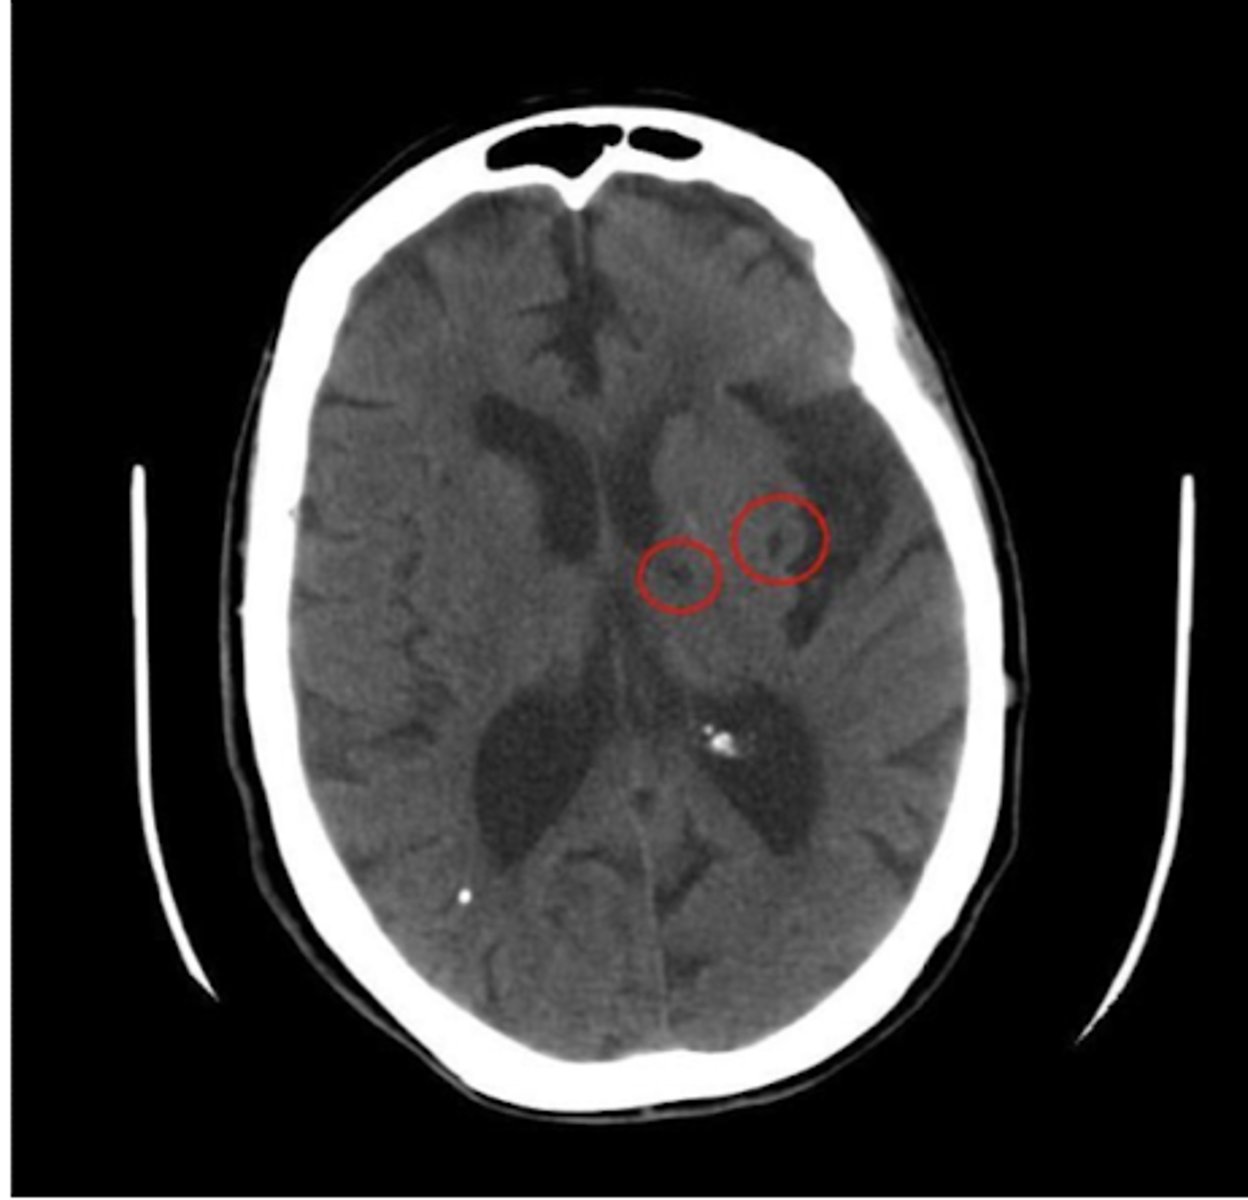

Circle of Willis with the most common sites for atheroma circled:

vessels in Circle of Willis = at risk of large artery atherosclerosis

in subcortical locations; basal ganglia and thalamus

Where do small vessel/Lacunar infarcts occur, and explain?

small, <1.5 cm in size

What is the size of small vessel/Lacunar infarcts like?

smaller lacunar infarct

old MCA infarct -> not the cause of death, but can see the changes/damage post-mortem from a previously experienced MCA infarct